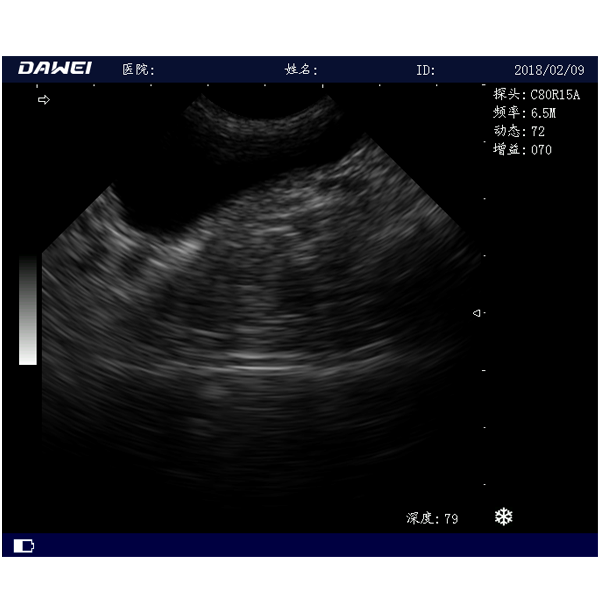

畜用b超机MT15是一款推车式兽用B超机拥有15英寸LED全视角显示器、宠物b超机性能稳定、图像清晰、支持≥5种变频的探头频率,可以给牛羊马猪犬猫及多种家禽、实验动物、小动物、及部分水生动物提供肝、胆,脾、肾、膀胱、妊娠等各组织器官的检查和病变的诊断。

三、畜用b超机MT15适用范围

中小动物的肝、胆,脾、肾、膀胱、子宫、妊娠等各组织器官的检查和病变的诊断